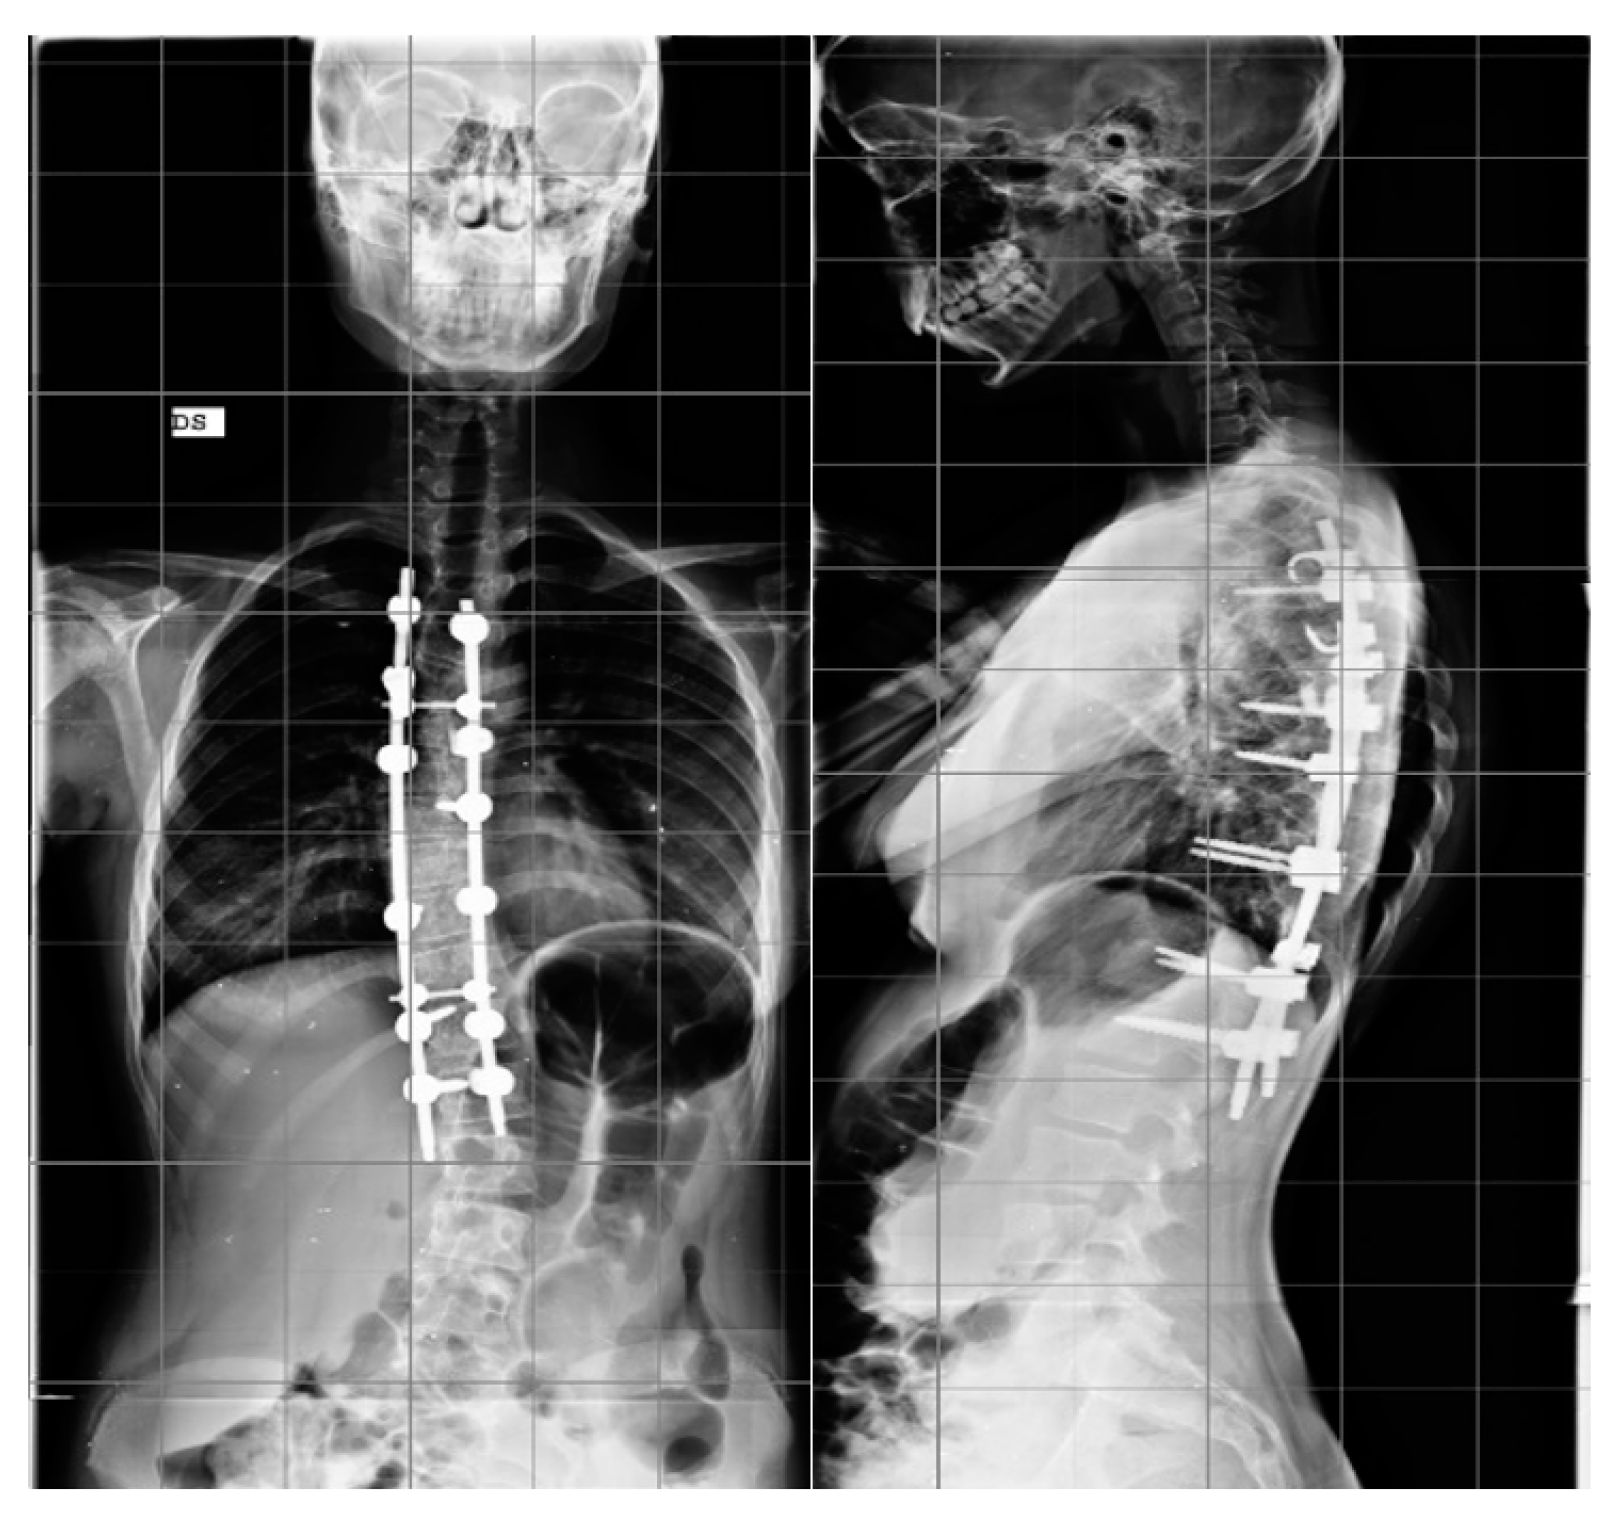

In patients treated with the hybrid technique, pedicle screws were inserted in the lumbar and inferior thoracic region generally up to T10. In the upper thoracic region, pedicle hooks were positioned with a cephalad direction. At the superior end in the convex side, a transverse process hook with a caudal direction was positioned to obtain a stable claw construct. In both techniques, a terminal box at the superior and inferior end of the fusion area was included (Figure 2).

Figure 2.

Example of hybrid construct for the treatment of AIS, AP, and LL.